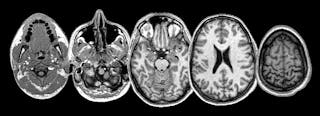

Cette année, cependant, dans un esprit de plaisir scientifique, mes collègues ont décidé de mettre cette vieille théorie à l’épreuve. Pour ce faire, ils ont réutilisé divers logiciels sophistiqués, conçus à l’origine pour l’analyse du cerveau par IRM. Alors que normalement ces outils écartent soigneusement tous les morceaux de crâne, permettant l’analyse du cerveau seul, ils les ont conçus pour faire l’inverse : reléguer tout le cerveau à la poubelle, en gardant au contraire les morceaux osseux pour l’analyse.

À partir de cette structure de surface, ils ont pu créer une carte détaillée des contours – des bosses – des crânes individuels. En tirant parti de la plus grande base de données d’imagerie cérébrale librement accessible au Royaume-Uni, les scientifiques ont acquis un échantillon massif de données provenant de près de 6 000 personnes. Outre les données cérébrales, cette base de données contient également une multitude d’informations provenant de questionnaires sur la démographie et le mode de vie, ainsi que des tests linguistiques et cognitifs de ses participants.